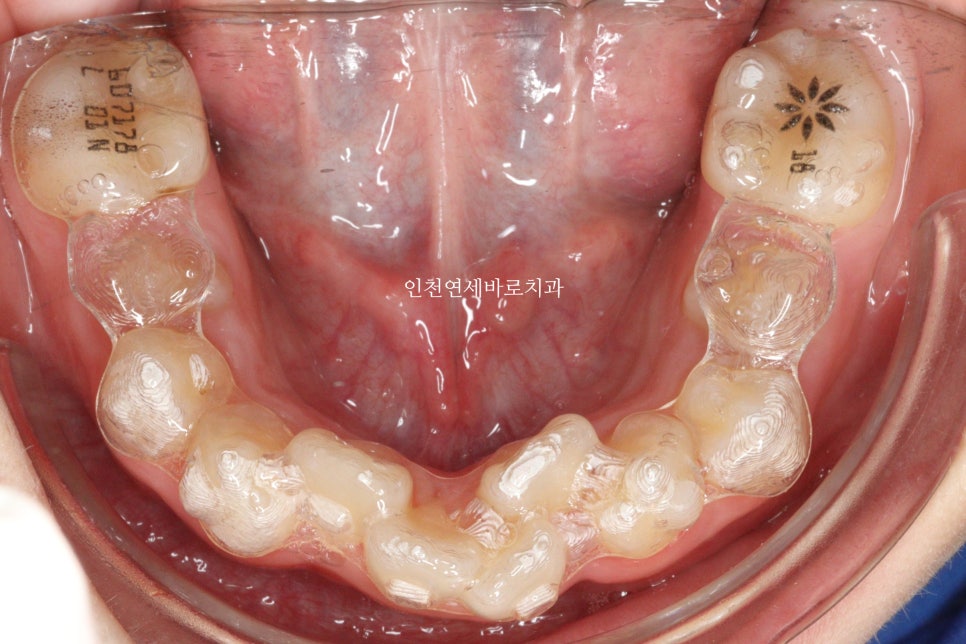

그리고 올해 12월 초에 병원에 왔을 때의 모습입니다.

100점은 아니지만, 이제는 거의 모든 치아가 배열된 것 처럼 보입니다.